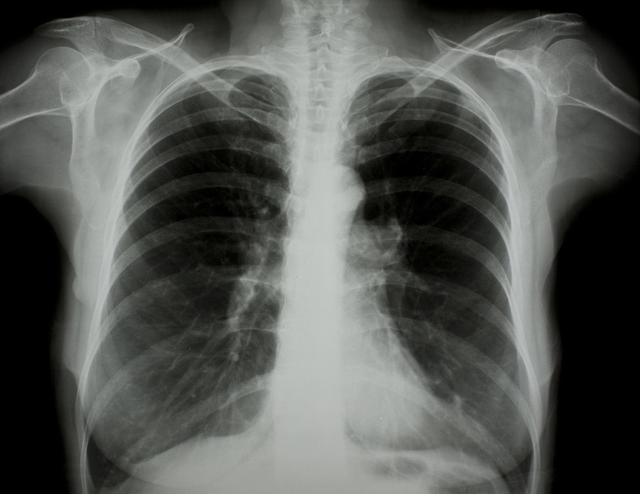

涪陵地區(qū)最新肺炎情況顯示,疫情形勢嚴(yán)峻。目前,當(dāng)?shù)卣歪t(yī)療部門正在積極應(yīng)對,采取一系列措施控制疫情傳播。具體感染人數(shù)、癥狀表現(xiàn)、疫苗接種情況等仍在持續(xù)更新中。請廣大市民密切關(guān)注官方發(fā)布的信息,做好個(gè)人防護(hù),共同抗擊疫情。涪陵地區(qū)肺炎疫情嚴(yán)峻,政府積極應(yīng)對,請市民關(guān)注官方信息,加強(qiáng)個(gè)人防護(hù)。

據(jù)最新官方數(shù)據(jù)顯示,涪陵地區(qū)肺炎病例數(shù)量令人擔(dān)憂,截至目前,涪陵地區(qū)累計(jì)確診肺炎病例XX例,疑似病例XX例,請大家務(wù)必提高警惕,不可掉以輕心。